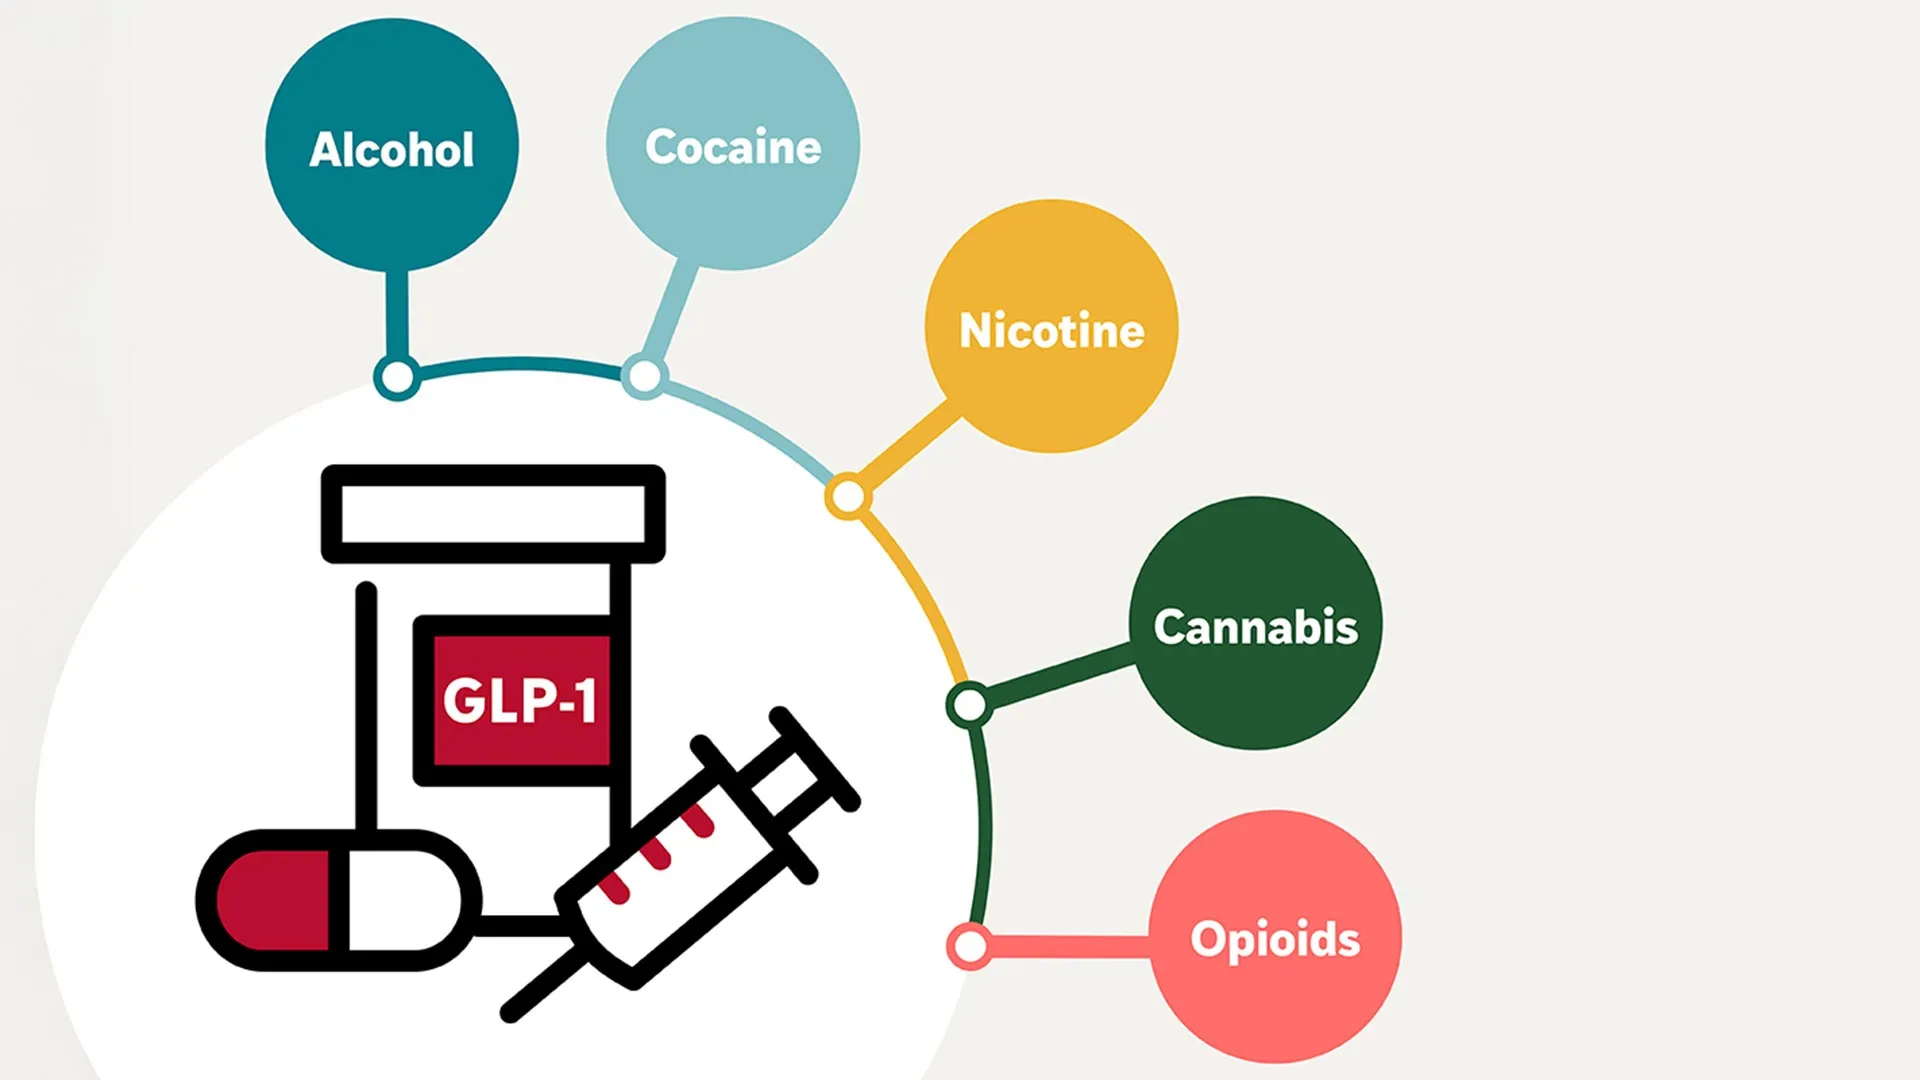

Popular GLP-1 drugs including Ozempic, Wegovy, Mounjaro, and Zepbound have already transformed the treatment of type 2 diabetes and obesity. Now, new research suggests these medications may also help prevent and treat addiction across a broad…